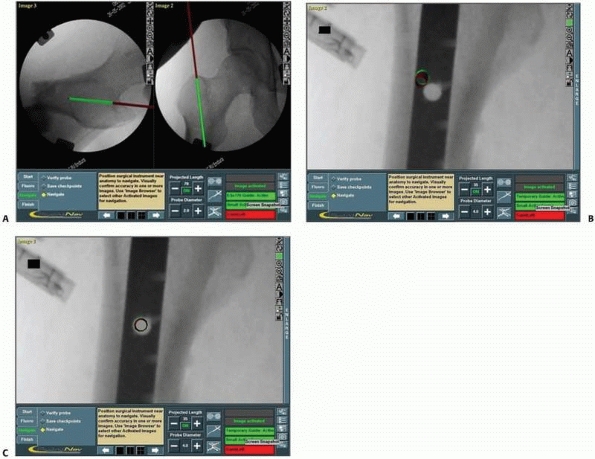

in the fixation of fractures or dislocations in the sacroiliac zone,

the acquired fluoroscopic views can be used for the insertion of more

than one screw (Figs. 17-13 and 17-14).

FIGURE 17-14 Sacroiliac and pubic ramus screw. A-C.

An intraoperative display of the computer screen during insertion of a sacroiliac screw and two intramedullary pubic ramus screws. D, E. Inlet and outlet postoperative verification radiographs showing the accurate real placement of the three screws. (Images property of authors.) |